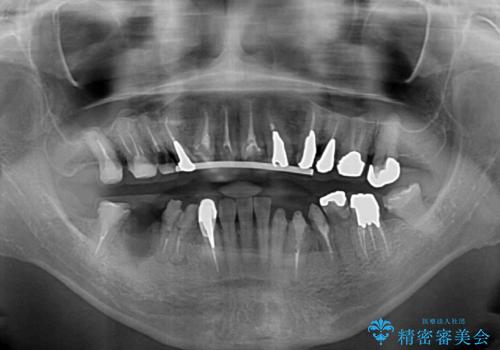

- 近医にて古いかぶせ物をセラミッククラウンにしようと治療を開始したものの、仮歯での咬み合わせが不安定とのことで、転院を希望して来院された患者様です。

骨格的に下顎骨が前方位に位置しており、上下前歯部の先端同士が接触する切端咬合でした。

このような方は咬み合わせが大きく変わると不安定となるため、まずは装着されている仮歯で咬合調整を行い、安定した咬み合わせとした後に、新しい仮歯に置き換え、その後オールセラミッククラウンにて補綴治療を行うこととしました。